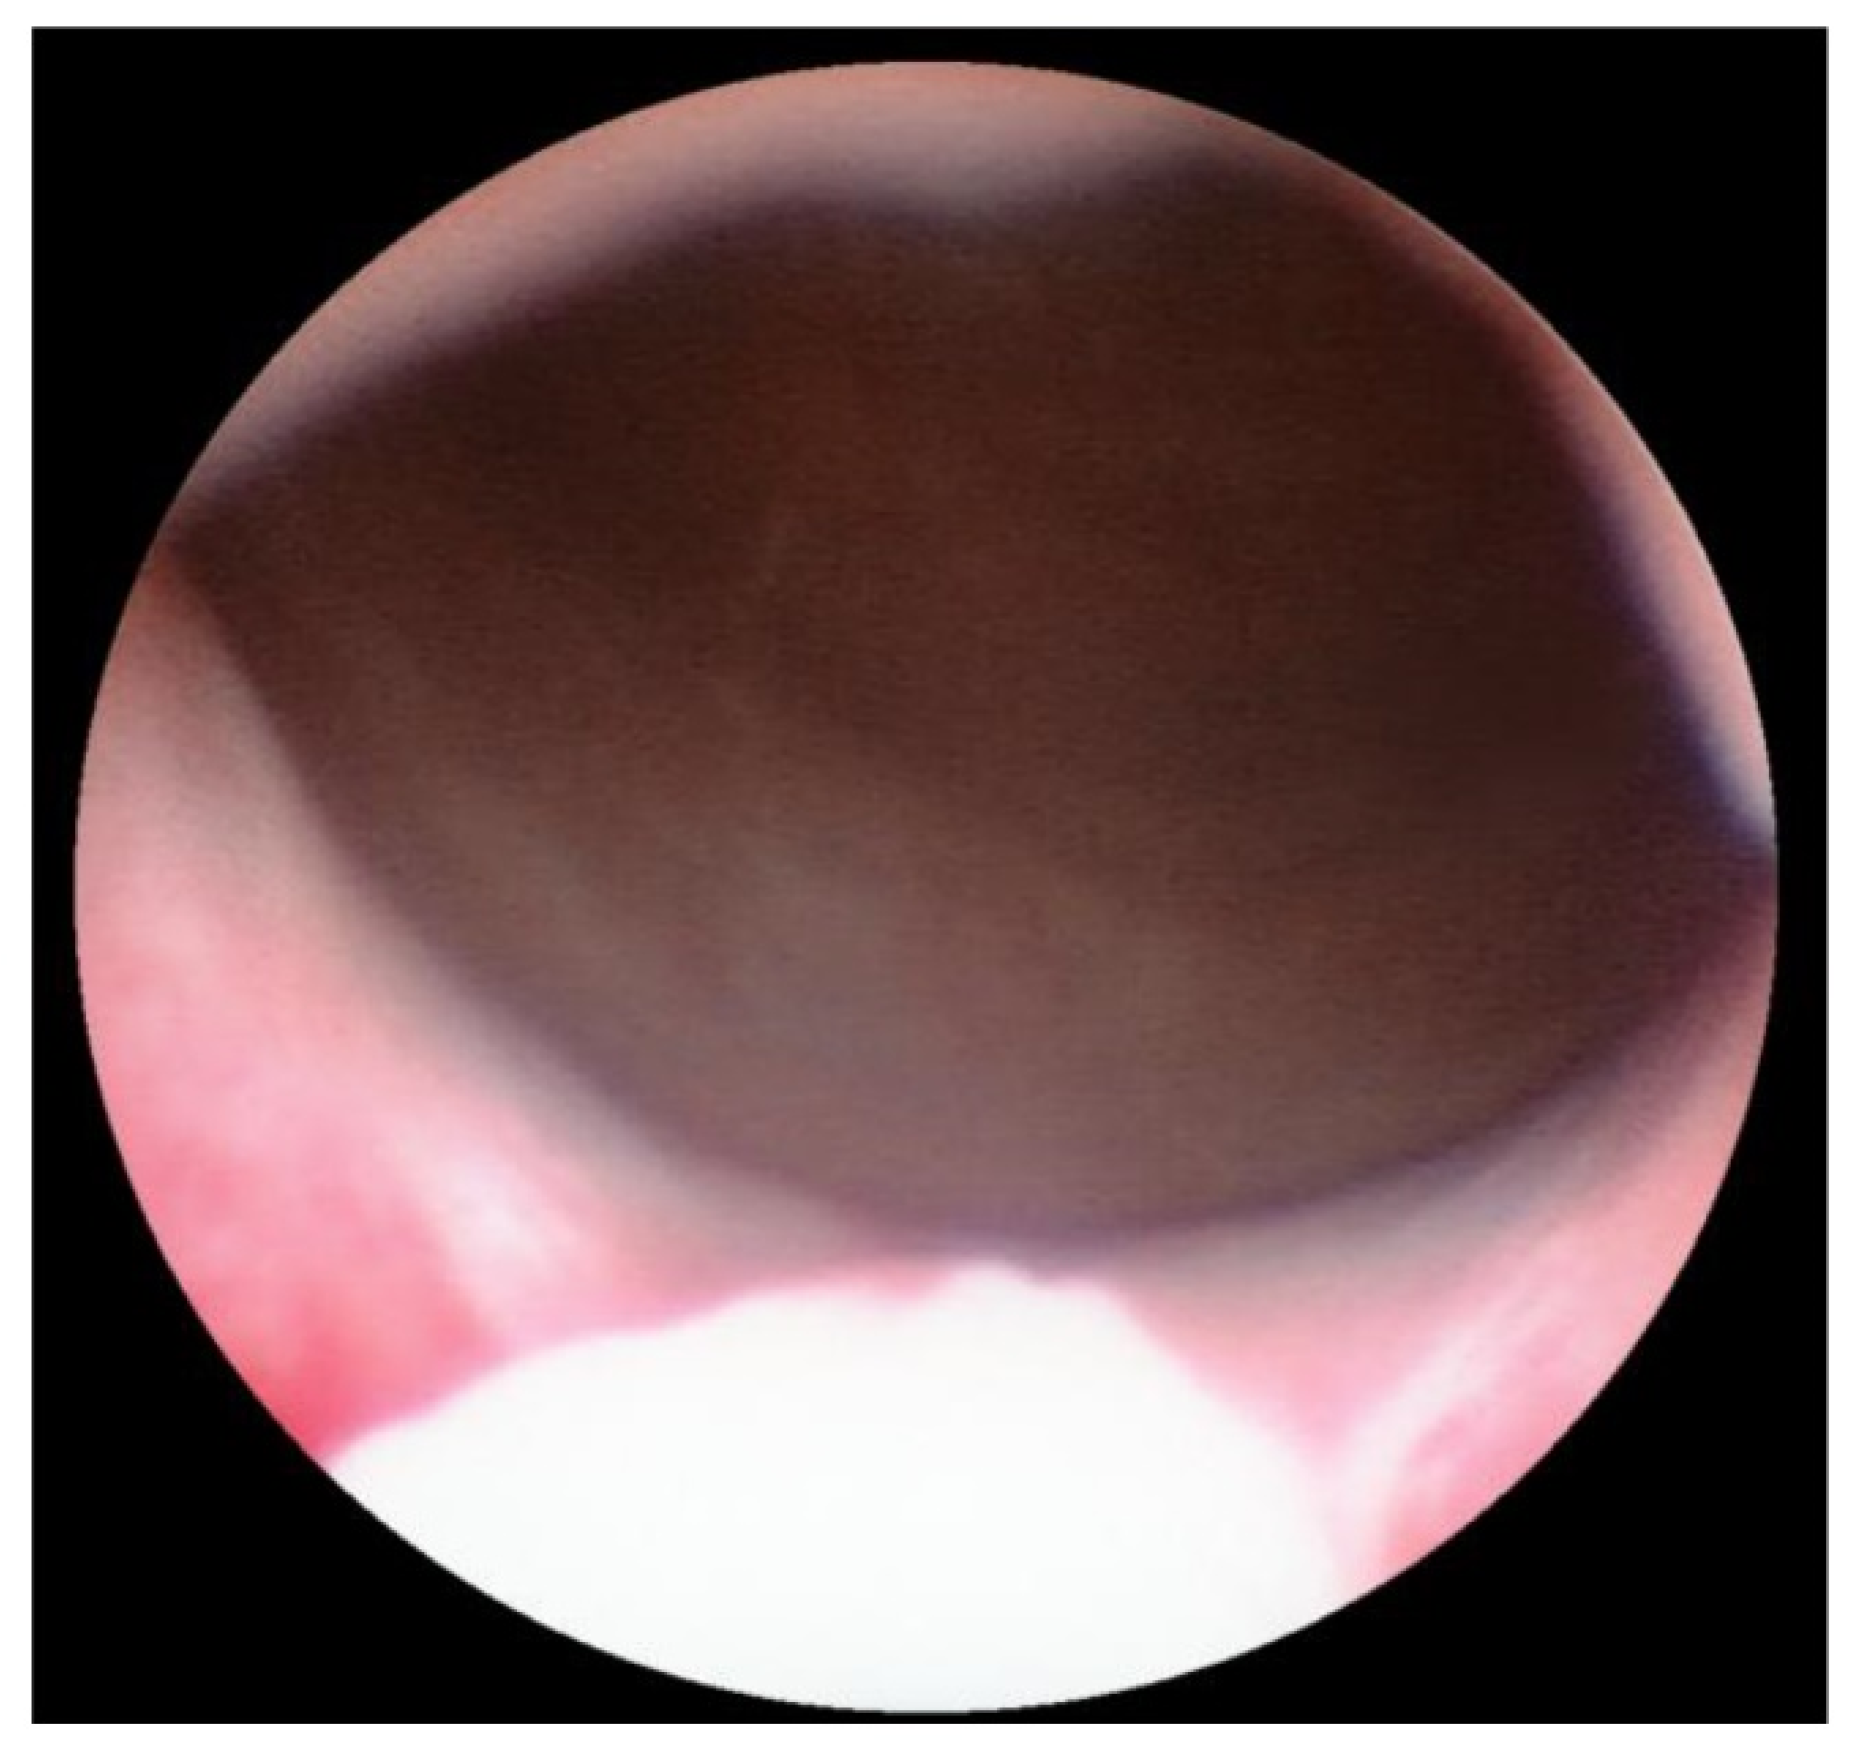

Transurethral cystoscopy displayed a wide open bladder neck at the beginning of the procedure (Figure 5). Under guidance by antegrade suprapubic endoscopy, transurethral retrograde bladder neck injection was performed at the 3 o’clock and 9 o’clock positions (Figure 6). Subsequently, bladder neck injection at the 6 o’clock and 12 o’clock positions was performed through antegrade percutaneous suprapubic endoscopy. Direct antegrade and retrograde visualization confirmed effectiveness of the luminal occlusion (Figure 7). As a (positive) consequence of effective injection, visibility of the optimal location for injection was compromised with increasing volume of the bulking agent. The combined injection technique is helpful to reduce this limitation as much as possible.

Figure 5.

Transurethral cystoscopy: wide open bladder neck.